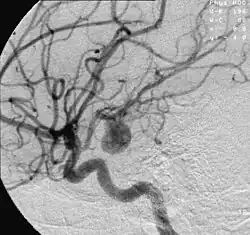

- Focal cerebral ischemia – A stroke occurring in a localized area that can either be acute or transient. This may be due to a variety of medical conditions such as an aneurysm that causes a hemorrhagic stroke, or an occlusion occurring in the affected blood vessels due to a thrombus (thrombotic stroke) or embolus (embolic stroke).[21] Focal cerebral ischemia constitutes a large majority of the clinical cases in stroke pathology with the infarct usually occurring in the middle cerebral artery (MCA).[22]